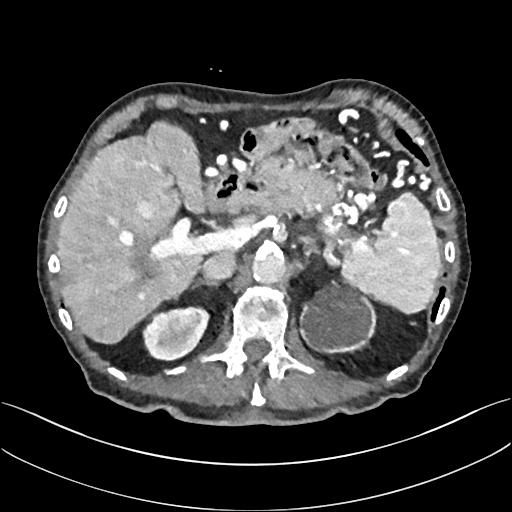

To demonstrate the effectiveness of the proposed network, we perform the qualitative comparisons over three representative abdominal images presented in Figs. 3, 5 and 7. For better evaluations of the image quality with different denoising models, zoomed regions-of-interest (ROIs) are marked by red rectangles and shown in Figs. 4, 6 and 8 respectively. Note that all results from different denoising models focus on two aspects: content restoration and noise-reduction. All CT images in axial view are displayed in the angiography window [-160, 240]HU.

The real NDCT images and corresponding LDCT images are presented in Figs. 3a and 3b. As observed, there are distinctions between ground truth (NDCT) images and LDCT images. Figs. 3a and 7a show the lesions/metastasis. Fig. 5a presents focal fatty sparing/focal fat. In Figs. 4a, 6a and 8a, these lesions can be clearly observed in NDCT images; in contrast, from Figs. 4b, 6b, and 8b, it can be seen that the original LDCT image is noisy, and lacks structural features for task-based clinical diagnosis. All adopted denoising models suppress noise to some extent.